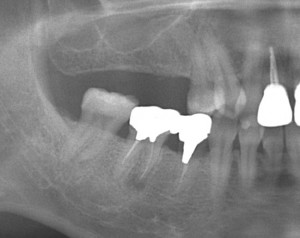

上顎臼歯部のソケットリフトによる骨造成をおこなった症例

上顎臼歯部のソケットリフトによる骨造成をおこなった症例をご紹介します。

K様 30代 女性

上顎の奥歯の方の骨がなく、ソケットリフトを用いて骨造成を行い、インプラントを埋入しました。

術前レントゲン写真です。

インプラント埋入直後のレントゲン写真です。

↑上のレントゲンを見ると、ドーム状に膨らんでいるのがわかります。

被せ物装着した後のレントゲン写真です。

↑最初薄かったレントゲン像が、周囲の骨と一体化し骨化したのがわかります。